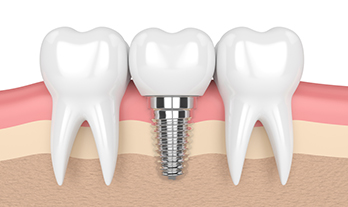

Dental Implant in College Road Nashik | Care32 Dental Clinic

Dental implants have revolutionized modern dentistry, offering a permanent and effective solution for missing teeth. If ...

Dental Implant in Canada Corner Nashik | Care32 Dental Clinic

A confident smile plays a crucial role in our self-esteem and overall well-being. However, missing teeth can lead to ora...